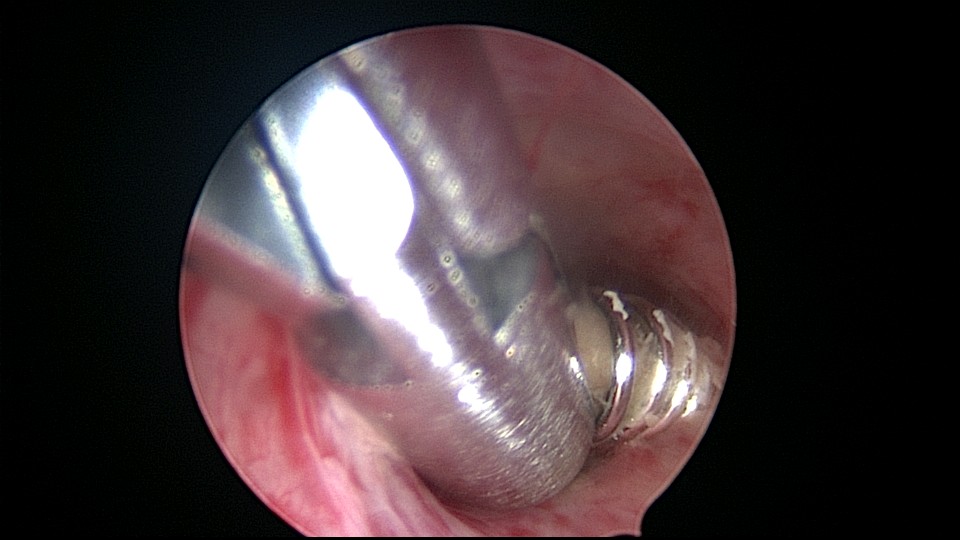

患者58岁,G2P1,顺产1次。安环35年,绝经15年,5年前在外院取环失败。术前B超提示子宫后位,O型环嵌顿,环顶端距宫底0.7cm。宫腔镜术中见阴道口狭小,无法置入窥阴器,宫颈外口狭窄,镜鞘缓慢扩大。宫颈内口粘连,左侧似有一小孔,异物钳扩大小孔,见较多浓稠黄色液体流出,冲洗干净后推进宫腔镜,见2个O型节育环,上面的环取出顺利,下面那个环与宫腔侧壁嵌顿,2次牵拉滑脱,第三次一张一驰松动节育环,再缓慢拉出,宫底见2道环压痕。